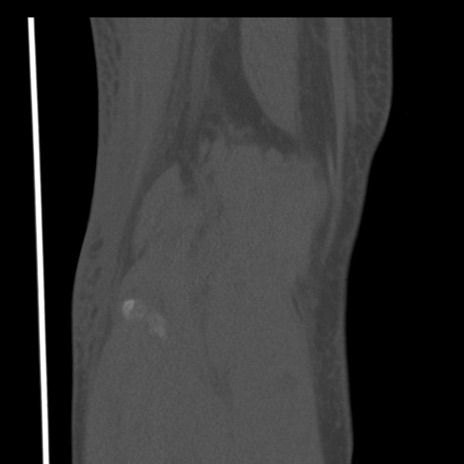

矢状断像